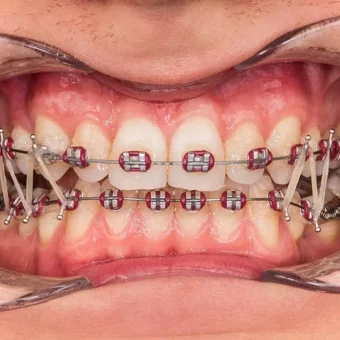

Druga wizyta w naszej klinice to czas na dokładne badania oraz diagnozę. Wykonujemy wtedy sesję zdjęciową – portretową oraz wewnątrzustną. Na podstawie tych materiałów dokonywana jest bardzo staranna analiza oraz projektowanie uśmiechu. Kolejny krok to zrobienie wycisków oraz przeprowadzenie rejestracji zgryzu. Jako jedna z nielicznych klinik w Polsce, Sobota House of Dentistry wprowadziła standardowo do procesu leczenia diagnozę mięśni i stawów pod kątem choroby okluzyjnej. Ta wiedza pozwala przeciwdziałać nawrotom wad zgryzu po kilku latach dzięki osiągnięciu idealnej harmonii zębów i stawów skroniowych. Dodatkowo eliminuje przyczyny i leczy objawy choroby okluzyjnej jakimi są m.in. ścieranie i zgrzytanie zębami, bóle w stawach skroniowo-żuchowwych, a nawet bóle głowy.

Podczas leczenia Pacjent jest pod stałą opieką nie tylko ortodonty, ale także profesjonalnej dyplomowanej higienistki, która dba o czystość zębów z aparatem ortodontycznym. Higienistka indywidualnie dobiera środki do higieny i metody oczyszczania zębów. Dodatkowo przeprowadza regularne fluoryzację zębów tak, aby zęby po zdjęciu aparatu były piękne i bez odbarwień.

Aparaty stałe

Są to systemy mocowane do zewnętrznych powierzchni zębów. Stosowane zamki ortodontyczne wykonane są z metalu. Zamki te nie niszczą szkliwa zębów, a ich rodzaj dostosowujemy do indywidualnych potrzeb Pacjenta. Popularne systemy:

- cienkołukowe (samoligaturujące i ligaturujące)

- lip bumper

- GMD